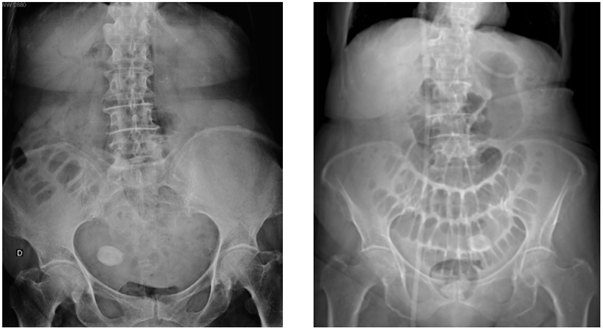

Mulher de 70 anos foi admitida no Pronto Socorro com queixa de náuseas, distensão e dores abdominais há 4 dias, com parada da eliminação de fatos e fezes há 1 dia. Patologias relatadas pela filha: obesidade, hipertensão arterial sistêmica e miomatose uterina. As imagens abaixo representam a radiografa simples da admissão (decúbito dorsal) e o topograma da tomografia computadorizada realizada 1 dia após.

Diante do quadro clínico e das imagens acima, assinale a alternativa que contém o diagnóstico correto.